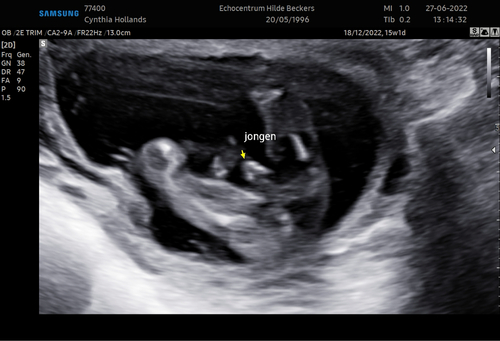

Dit is geen nub meer, dit is gewoon het geslacht van de baby voor degenen die dat kunnen zien.

Dit is geen nub.

Inderdaad deze echo laat echt het geslacht zien.